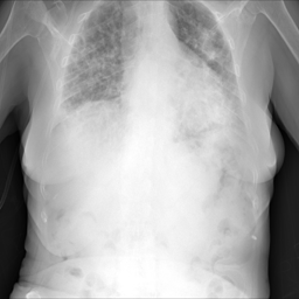

Samples of the dataset are depicted in Figure 3.

The dataset is arbitrarily partitioned among each client (). , and then the prediction performance results in the encrypted-domain are compared with the results of the plain-domain.